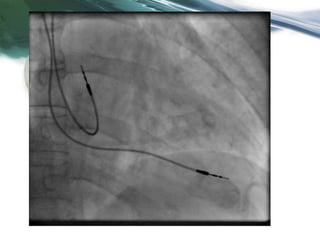

Case Study #2 Screenshot

Case Study #2 Questions

• What do you see? According to the device, how fast was the

patient’s rhythm before the delivered shock? (130ms)

• How fast was the patient’s actual rhythm? (620ms) How can

you tell? (EGM 2 Vtip-Vring shows true V complexes)

• How do you account for the discrepancy? (noise/EMI)

• What steps can be taken to prevent future inappropriate

shocks for this patient and future patients who have

surgical procedures at the facility? (magnet use during

surgery)